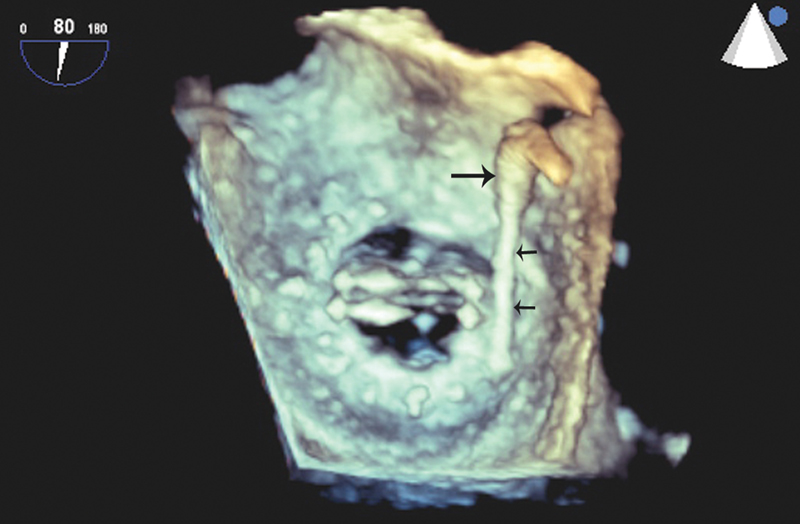

فحوصات تشخيصية لبعض امراض القلب والشرايين التاجية